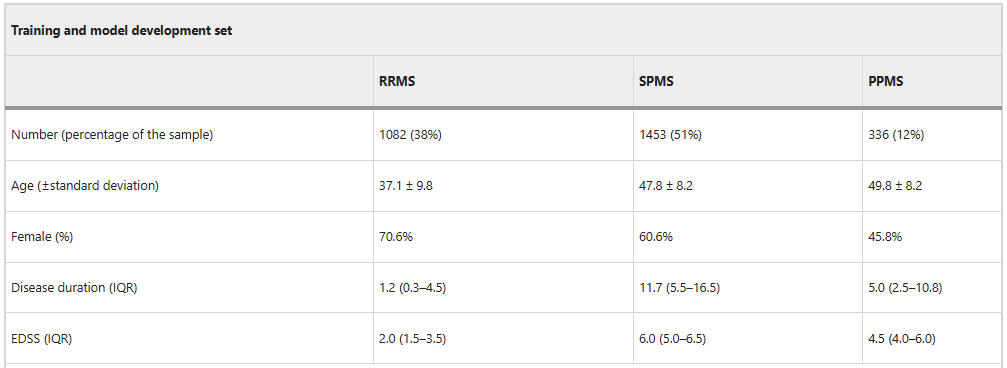

在模型训练阶段,研究人员使用了 8,550 张真实和合成图像的数据集对 MindGlide 进行训练。其中,真实的 MRI 扫描图像共计 4,247 张(包括 2,092 张 TI-weighted 和 2,155 张 FLAIR),来自 2,871 名患者(包括 1,082 名复发缓解型 MS 患者 (RRMS)、1,453 名继发进行型 MS 患者 (SPMS) 和 336 名原发进行型 MS 患者(PPMS))。这些扫描图像通过 592 台专业的 MRI 扫描仪器分别在 1.5 和 3 特斯拉磁场下获得。随后,研究人员又生成了 4,303 张合成扫描图像来扩展训练。

训练集的患者特征